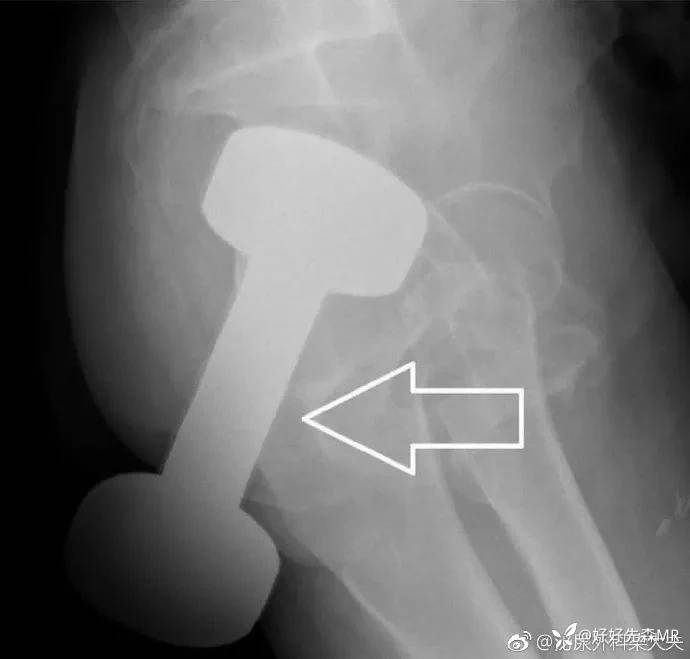

甚至还有人将10斤的哑铃塞进肛门!!!